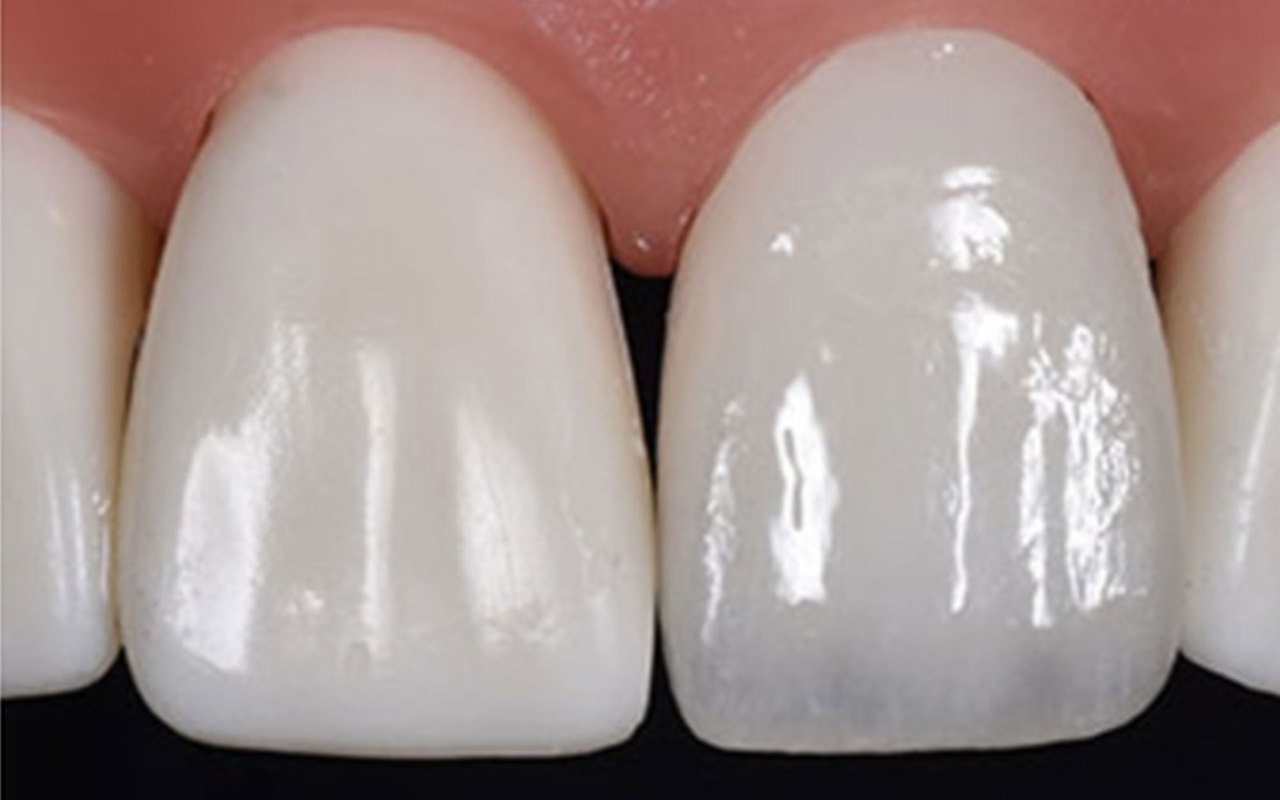

- 자연치와 유사한 색상 구현 가능

어금니는 하루에도 수천 번 씹는 힘이 전달되는 부위이기 때문에 보철물의 강도가 매우 중요합니다. 금속 크라운도 강도가 높지만 심미성이 떨어지는 단점이 있습니다. 반면 지르코니아 크라운은 강도와 심미성을 동시에 만족시키는 재료이기 때문에 최근 치과에서 가장 많이 선택되는 크라운 재료 중 하나입니다.

특히 지르코니아는 종류에 따라 강도와 투명도가 다릅니다. 강도가 높은 대신 색이 덜 자연스러운 지르코니아도 있고, 심미성이 뛰어난 대신 강도가 조금 낮은 재료도 있습니다. 이러한 재료 선택에 따라 가격이 달라질 수 있습니다.